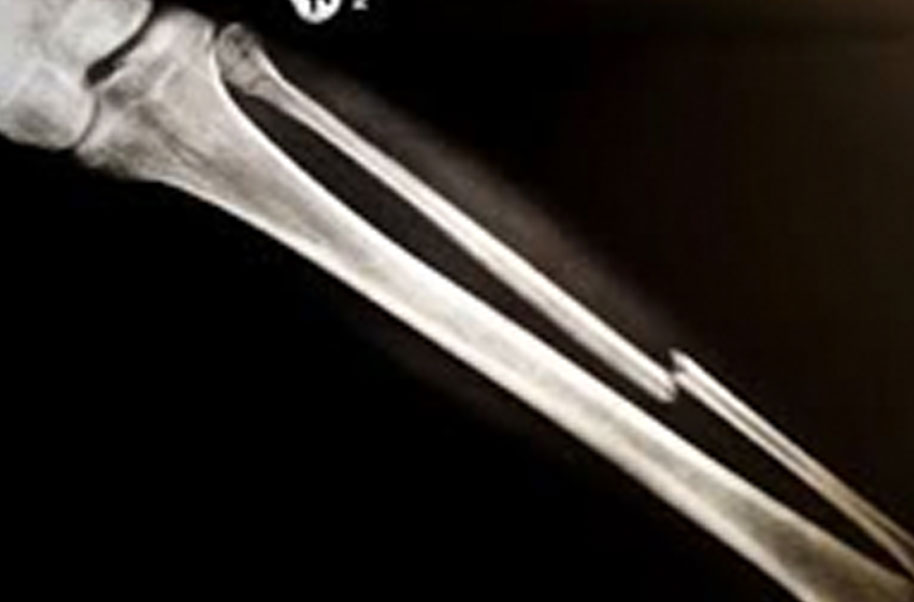

Sesamoid (Broken Bone)

A complete or partial break in a bone.

- Treatment often involves resetting the bone in place and immobilising it in a cast or splint to give it time to heal. Sometimes, surgery with rods, plates and screws may be required.

Causes of bone fractures include trauma, overuse and diseases that weaken bones.